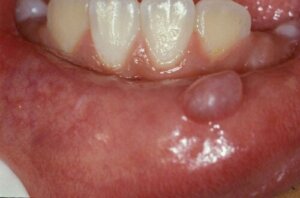

Obecnie uważa się, że śluzowiak jest najczęstszą łagodną zmianą w jamie ustnej człowieka. To nic innego jak niewielka torbiel wypełniona śluzem, która tworzy się w miejscach, w których znajdują się drobne gruczoły ślinowe. Badania szacują, że 96% mucocele występuje na dolnej wardze.

Są to łagodne zmiany torbielowate powstałe w wyniku zaburzenia drobnych gruczołów ślinowych. Zwykle same zawierają śluz, są też wyścielone komórkami śluzowymi. Mogą być powierzchowne lub głębokie i różnić się wielkością od kilku milimetrów do 3 centymetrów.

Śluzowiak objawia się nagle małym pęcherzem lub guzkiem wypełnionym śluzem w jamie ustnej, zwykle na dolnej wardze. Może mieć półprzezroczysty niebieski kolor lub utrzymywać ten sam odcień co błona śluzowa. Są to zmiany bezbolesne, chyba że dodatkowo towarzyszy im rana.

Niektórzy ludzie często mylą je z owrzodzeniami. Jednak te ostatnie stanowią wrzodziejące zmiany z czerwonawymi krawędziami i białymi środkami, które powodują też ból i dyskomfort. Chociaż najczęstszą lokalizacją jest dolna warga, mogą również tworzyć się na języku, podniebieniu, błonie śluzowej policzka i dnie jamy ustnej.